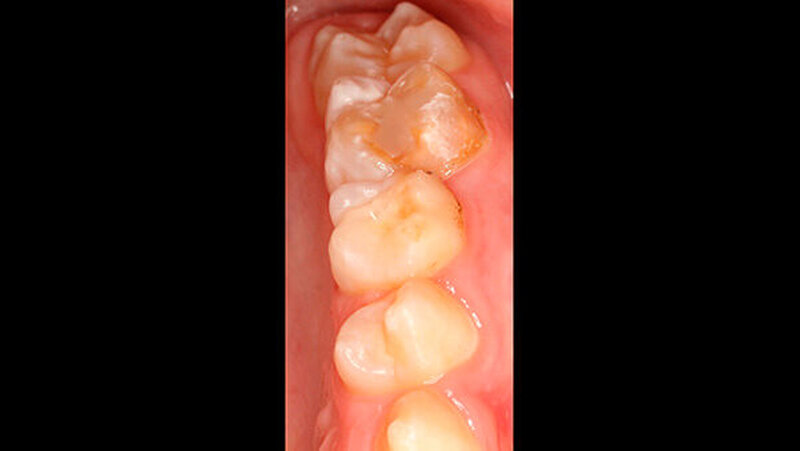

Der Zahnwechsel im 2. Quadranten war noch nicht vollständig, dasselbe galt für den Unterkiefer (Abbildungen 4 und 5). Im Unterkiefer war insbesondere die Opazität und der bukkale Schmelzeinbruch (inklusive der Reste einer adhäsiven Füllung) an Zahn 85 deutlich sichtbar.

Zusätzlich wiesen beide Sechsjahrmolaren im Unterkiefer insbesondere im Bereich der Höcker (46) sowie der Höckerspitzen (36) ebenfalls Opazitäten auf, deren farbliche Veränderung von milchig-weiß bis hellbraun reichte. Zahn 46 war darüber hinaus mit einer erweiterten Fissuren-Versiegelung oder einer kleinen okklusalen Füllung versorgt. Das Trocknen der Seitenzähne mittels Luft rief ein geringfügiges Schmerzgefühl bei dem Patienten hervor, an Zahn 26 allerdings eine starke Sensibilität.